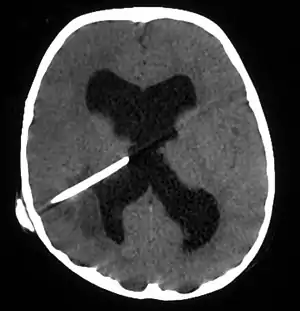

| Brain abscess in a person with a CSF shunt.[1] | |

The diagnosis is established by a computed tomography (CT) (with contrast) examination. At the initial phase of the inflammation (which is referred to as cerebritis), the immature lesion does not have a capsule and it may be difficult to distinguish it from other space-occupying lesions or infarcts of the brain. Within 4–5 days the inflammation and the concomitant dead brain tissue are surrounded with a capsule, which gives the lesion the famous ring-enhancing lesion appearance on CT examination with contrast (since intravenously applied contrast material can not pass through the capsule, it is collected around the lesion and looks as a ring surrounding the relatively dark lesion). Lumbar puncture procedure, which is performed in many infectious disorders of the central nervous system is contraindicated in this condition (as it is in all space-occupying lesions of the brain) because removing a certain portion of the cerebrospinal fluid may alter the concrete intracranial pressure balances and causes the brain tissue to move across structures within the skull (brain herniation).

CT guided stereotactic aspiration is also indicated in the treatment of brain abscess. The use of pre-operative imaging, intervention with post-operative clinical and biochemical monitoring used to manage brain abscesses today dates back to the Pennybacker system pioneered by Somerset, Kentucky-born neurosurgeon Joseph Buford Pennybacker, director of the neurosurgery department of the Radcliffe Infirmary, Oxford from 1952 to 1971. [12]